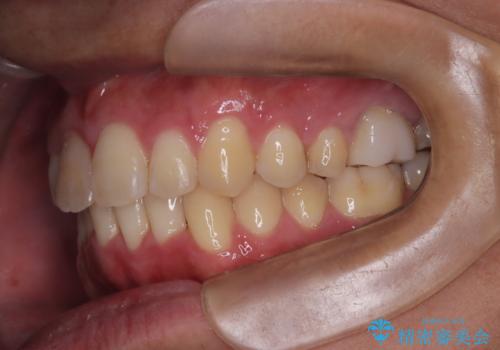

【インビザライン 非抜歯】歯の捻じれと歯のでこぼこを治したい!

- 「上の前歯の捻じれと下の前歯のでこぼこを治したい」を主訴に来院された患者様です。

矯正検査の結果、非抜歯で矯正可能だったためインビザラインで治療を行いました。

アーチの拡大とIPRで叢生を改善いました。

11ヵ月で矯正を終える事ができ患者様も大変ご満足されていました。